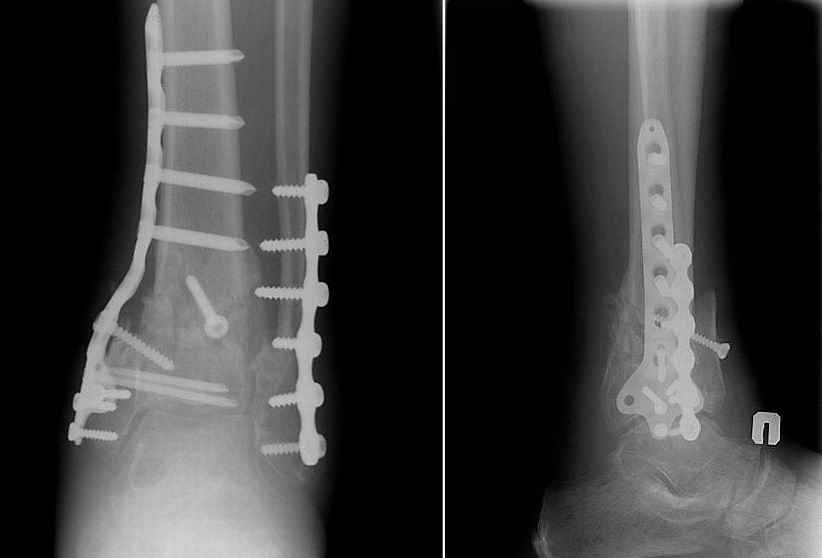

На снимке типичный перелом пилона с компрессией метафиза и с укорочением берцовой кости. Свежие переломы пилона лечатся восстановлением длины малоберцовой и с замещением дефекта большеберцовой структурным пластическим материалом. Обычная аутокость или синтетические заполнители служат пластическим материалом. В зависимости от перелома пластину устанавливают медиально или латерально.

Без восстановленного метафизарного дефекта перелом пилона со временем коллапсируется, а малоберцовая удерживает нагрузку и конечность деформируется в варус.

Для создания опороспособности конечности я бы рекомендовал исправить ось остеотомией малоберцовой. Фиксация малоберцовой создаст латеральную стабильность. Идеальный мортизный снимок подскажет, насколько надо укоротить малоберцовую.

Наличие медиальной (locking) пластины не обязательно, хотя установленная щадящим (перкутанно) методом пластина даст уверенность.

Прооперировали 6 февраля.

На операции - несращение проксимального диафизарного отломка и осколков эпифиза, которые представляли собой неправильно сросшийся, крепкий конгломерат. С учетом сохранности движений в голеностопном суставе (боясь ему навредить), решено было не разбирать их, а только исправить ось голени, что и было сделано, после остеотомии и резекции малоберцовой кости + остеопластика.

Получилось видимо не идеально, внушает оптимизм хорошее состояние мягких тканей и сохранность движений в голеностопном суставе после операции. Хотя... :)